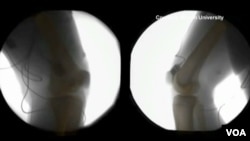

Quhet XROMM ose Rindërtimi i Radioskopisë së Morfologjisë së Lëvizshme, dhe është një mënyrë e re për të parë brenda trupave të njerëzve dhe kafshëve.

Tomografia jep imazhin e formës së kockës. Duke i shtuar filmimet radioskopike, shkencëtarët mund të krijojnë animacione tre dimensionale që duken si pamje filmike të pjesëve të brendshme të trupit.

“Me kombinimin e XROMM-it dhe fluoromikrometrisë ne mund të shtojmë muskujt tek ky animacion në mënyrë që të kuptojmë sesi kockat dhe muskujt bashkëveprojnë për të krijuar lëvizjen”, thotë zonja Brainerd.